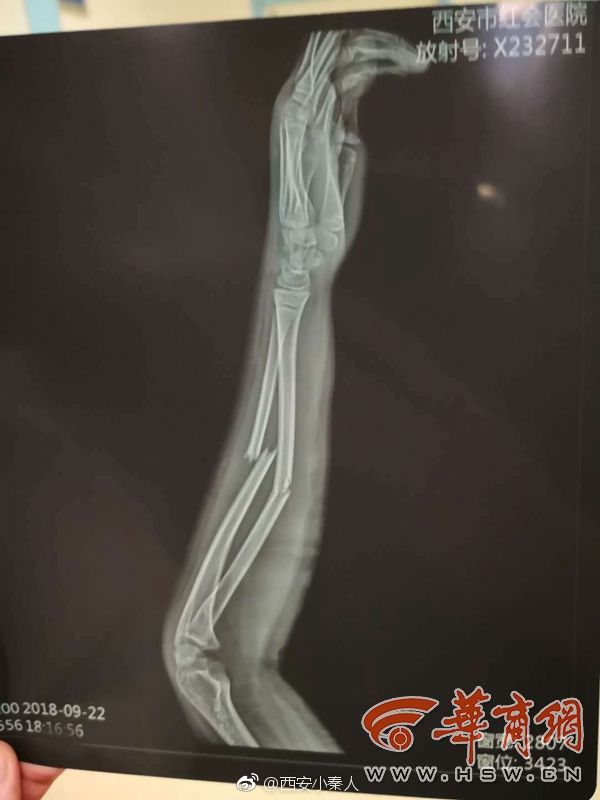

胳膊骨裂图片,胳膊骨折图片真实

胳膊骨折图片真实

胳膊骨裂片子图片

胳膊骨裂图片x光